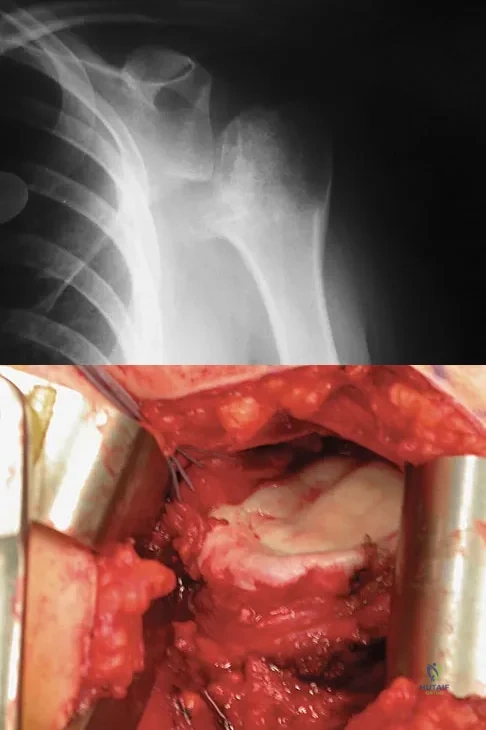

A 28-year-old man sustained a shoulder dislocation 2 years ago. It remained dislocated for 3 weeks and required an open reduction. He now reports constant pain and has only 60 degrees of forward elevation and 10 degrees of external rotation. He desires to return to some sporting activities. An AP radiograph and intraoperative photograph (a view of the humeral head through a deltopectoral approach) are shown in Figures 31a and 31b. What is the best treatment option to decrease pain and improve function?

Explanation